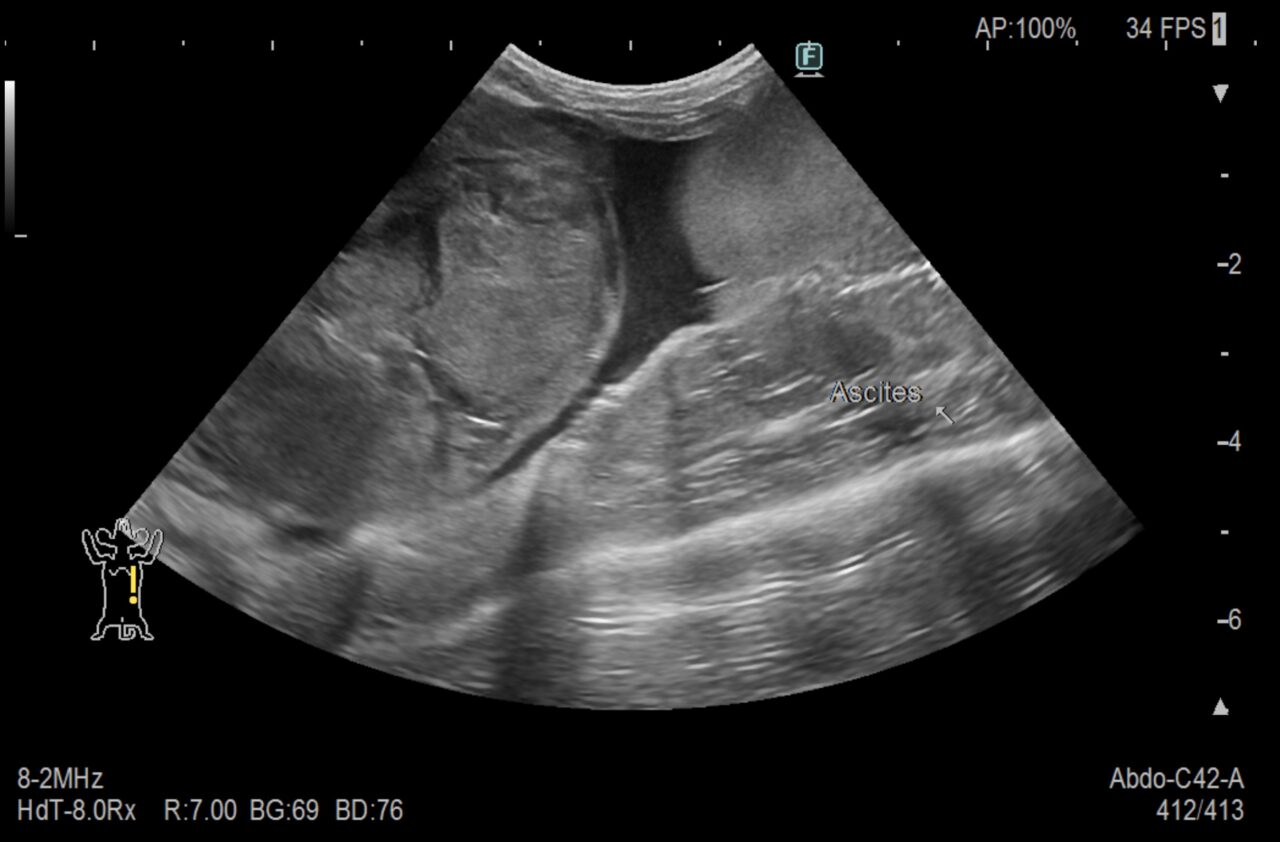

腹部エコーを確認すると脾臓に巨大な腫瘍があり、腹水(おそらく出血)が見られたためこの腫瘍が破裂したものと判断しました。